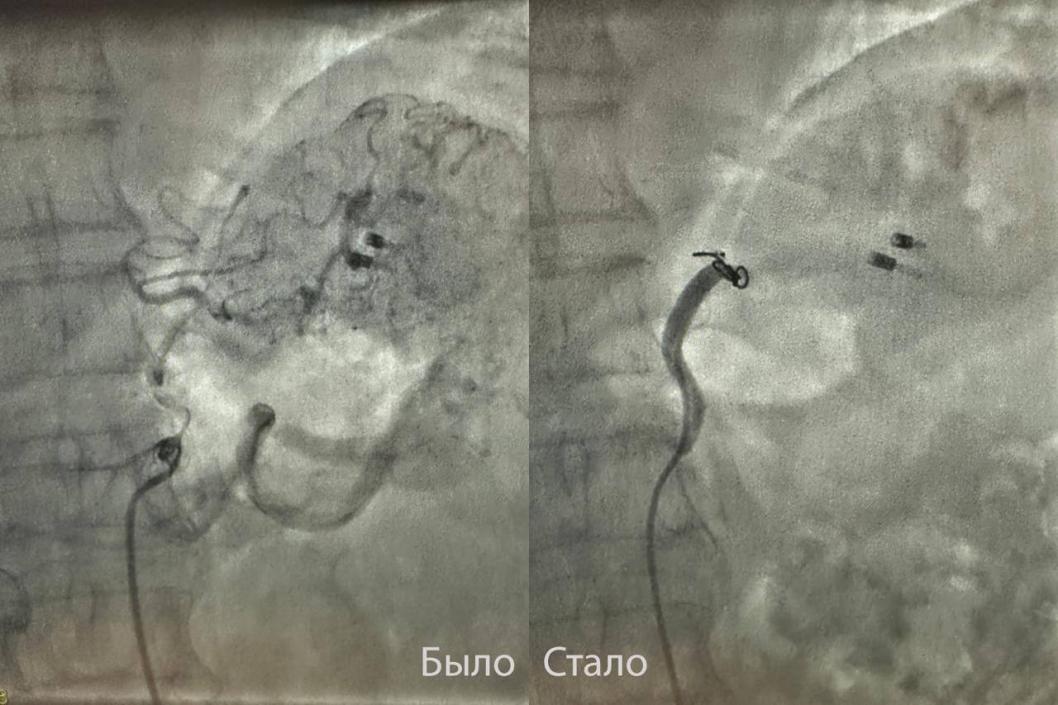

В тюменскую Областную больницу № 3 поступила женщина с язвой желудка размером пять сантиметров, которая сопровождалась сильнейшим кровотечением. Хирурги спасли пациентку, проведя операцию без разрезов. Об этом рассказали в пресс-службе больницы.

Заведующий хирургическим отделением Семен Франц принял решение использовать альтернативный, менее травматичный метод. Совместно с хирургом Андреем Прохорихиным они провели эндоваскулярную операцию: через маленький прокол в бедре врачи нашли кровоточащий сосуд и перекрыли в нем кровоток с помощью специальной спирали и медицинского клея.

– Учитывая, что желудок имеет несколько источников кровоснабжения, «отключение» одного из них оказалось безопасным и жизненно необходимым, – пояснил Семен Франц.

В результате этого вмешательства удалось полностью остановить кровотечение и избежать рискованной полостной операции. Через неделю состояние пациентки стабилизировалось, угроза жизни была устранена, и ее перевели на домашнее лечение.